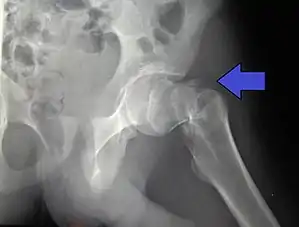

Fracture supported by dynamic hip screw

A trochanteric fracture, below the neck of the femur, has a good chance of healing.

Closed reduction may not be satisfactory and open reduction then becomes necessary.[42] The use of open reduction has been reported as 8-13% among pertrochanteric fractures, and 52% among intertrochanteric fractures.[43] Both intertrochanteric and pertrochanteric fractures may be treated by a dynamic hip screw and plate, or an intramedullary rod.[42]

The fracture typically takes 3–6 months to heal. As it is only common in elderly, removal of the dynamic hip screw is usually not recommended to avoid unnecessary risk of second operation and the increased risk of re-fracture after implant removal. The most common cause for hip fractures in the elderly is osteoporosis; if this is the case, treatment of the osteoporosis can well reduce the risk of further fracture. Only young patients tend to consider having it removed; the implant may function as a stress riser, increasing the risk of a break if another accident occurs.